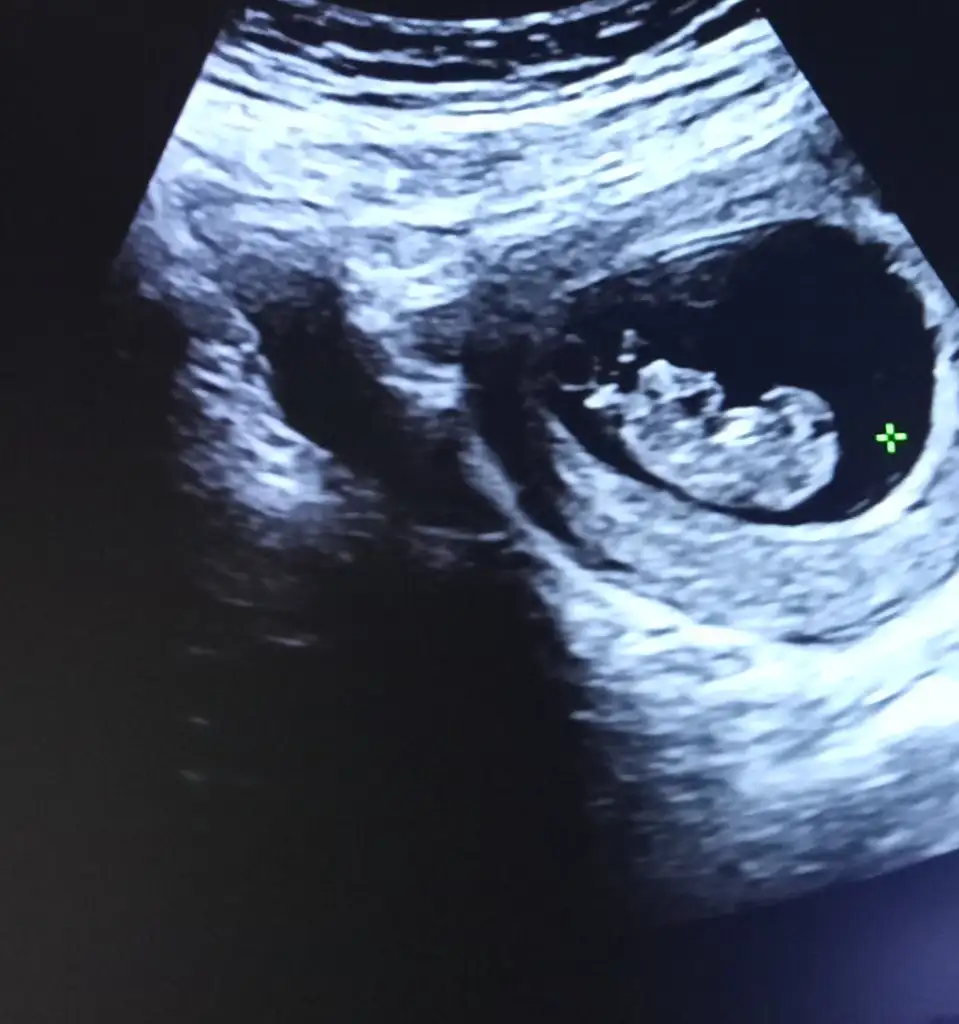

Ya aslında yapacaktı ama ben cinsiyet partisi yapabilirim deyince biraz daha bekleyelim dedi 11.haftamızdaAy maşallahhh. Cinsiyetiyle ilgili tahmin yaptı mı doktor?

bende 3 hafta sonra ikil teste gidicem de devlette 16ya kadar söylemiyolar diyolar..inşallah smyler. Herkes erkeğe benzetti ama benim hissim kızYa aslında yapacaktı ama ben cinsiyet partisi yapabilirim deyince biraz daha bekleyelim dedi 11.haftamızdabir dahaki kontrol 23 Eylül. O zaman yazacak kağıda nasipse

Kaç haftalıksın? Brnim cildim bi parladı gbi ama kız annelerininde güzelleştiğini duymuştum. Her hamilelik aynı değil cidden. Paylaşmak istersen usg görüntüsüne bakablr miyim? Benim hisler tutuyoYani sonuçta herkes farklı yaşıyor gebeliği, tabiki de merak ediyor insan ama herkesin de ayrı yorum yapmasıbana da herkes erkek diyor ultrason görüntüsünden dolayı ama zaten benimm için sağlıklı olması önemli. Ama yüzüm solgun mesela o cilde gelen parlaklık bana gelmedi bana doktor bey azcik tahmin etseydi ama hiç etmedi :/

o vajinalde oluyor diye biliyorum. Karından ayna gibi sağ tatafındaysa aslında sağ tarafında oluyor. Bneim kesem sağda mesela çünkü hep sağda şişlik var13+3, aslında değişiyor cildim bazen iyi gözüküyor bazense solgun oluyorum bazen mesela çok halsiz bazense aşırı enerjiğimannemlerde kalıyorum canım eşim şehir dışına çıktı eve geçtigimde unutmazsam atarım, sizin ki nerde sağ da mı sol da mı ? Bazıları da ultrason fotosunda sağdaysa aslında soldadir falan diyor o nasıl oluyor

Oyy maşAllaho vajinalde oluyor diye biliyorum. Karından ayna gibi sağ tatafındaysa aslında sağ tarafında oluyor. Bneim kesem sağda mesela çünkü hep sağda şişlik var

benim ilk sağdaydı sola geçti ama bende hep erkek bebek solda olue diye duydumOyy maşAllahRabbim sağlıkla ve hayırla kucağınıza almayı nasip etsin ama ben kız gibi hissettim birden öyle hissettim, genelde bebek solda olunca kız sağda ise erkek derler ama yime de herkeste tutmayabilir. Sonuçta her yerde hareket ediyorlar bebişlerimiz